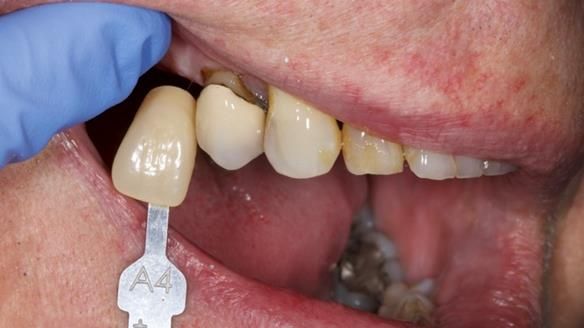

Welcome to Newsletter 64. I'll walk you through the process of providing a Mk 2 metal-based partial denture (RPD), for Ian a retired Veterinary Surgeon aged 78. The RPD was made at an increased vertical dimension and acted as an occlusal stabilisation splint - reducing the wear and bite force on the remaining natural teeth.